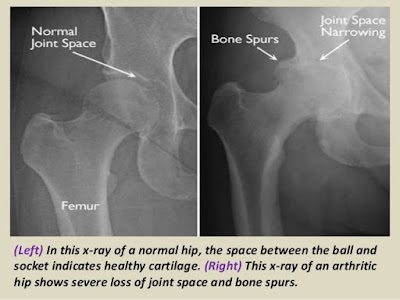

X- Ray மூலம் மூட்டுக்களை அவதானிக்குபோது இவற்றை இலகுவாக கண்டறியலாம்.

X Ray, MRI மூலமே இன் நோயை உறுதிப்படுத்தலாம்.